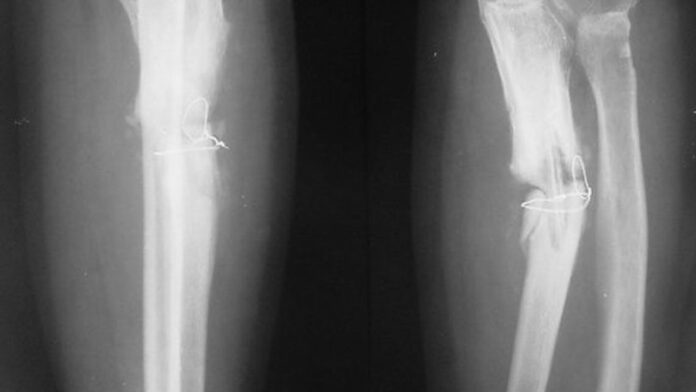

Cercetătorii chinezi susţin că au dezvoltat un adeziv osos care poate fi folosit pentru a trata fracturile şi fragmentele osoase zdrobite, printr-o procedură care durează doar trei minute.

Cercetătorii chinezi susţin că au dezvoltat un adeziv osos care poate fi folosit pentru a trata fracturile şi fragmentele osoase zdrobite, printr-o procedură care durează doar trei minute.